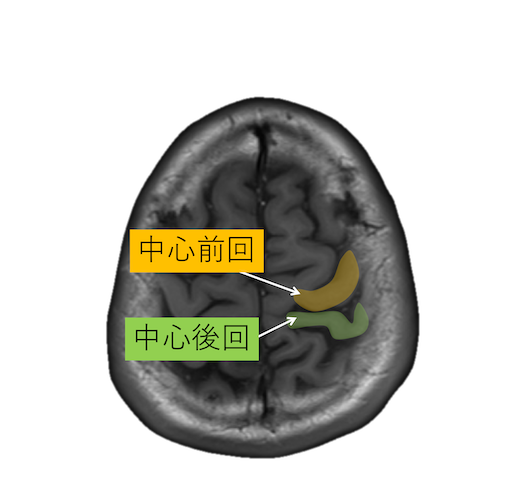

中心溝、中心前溝、中心後溝、中心前回、中心後回のMRI画像における解剖

主に脳梗塞診断などで重要な中心溝、中心前溝、中心後溝、中心前回、中心後回のMRI画像における解剖(CTでも使えます。)をご覧いただけます。

・脳回の前後幅は中心前回が後回より太い。

・中心前回の手指運動野は後方凸を示す(precentralknob sign)